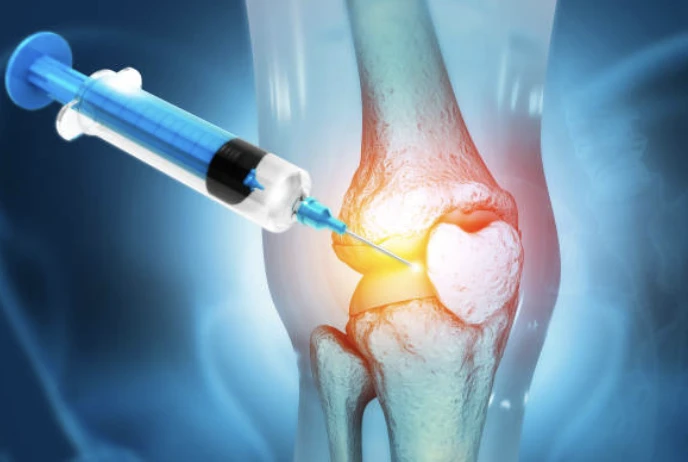

무릎 통증 치료방법

- 증식치료 : 비수술치료로 약해진 인대를 튼튼하게 강화시켜 주는 간편 주사 시술입니다.

- 도수치료 혹은 물리치료

- 운동을 통한 무릎 주변 근육 성장

- 수술을 통한 치료 : 내시경술, 근위경골 절골술, 인공관절 부분치환술, 인공관절 전치환술 등